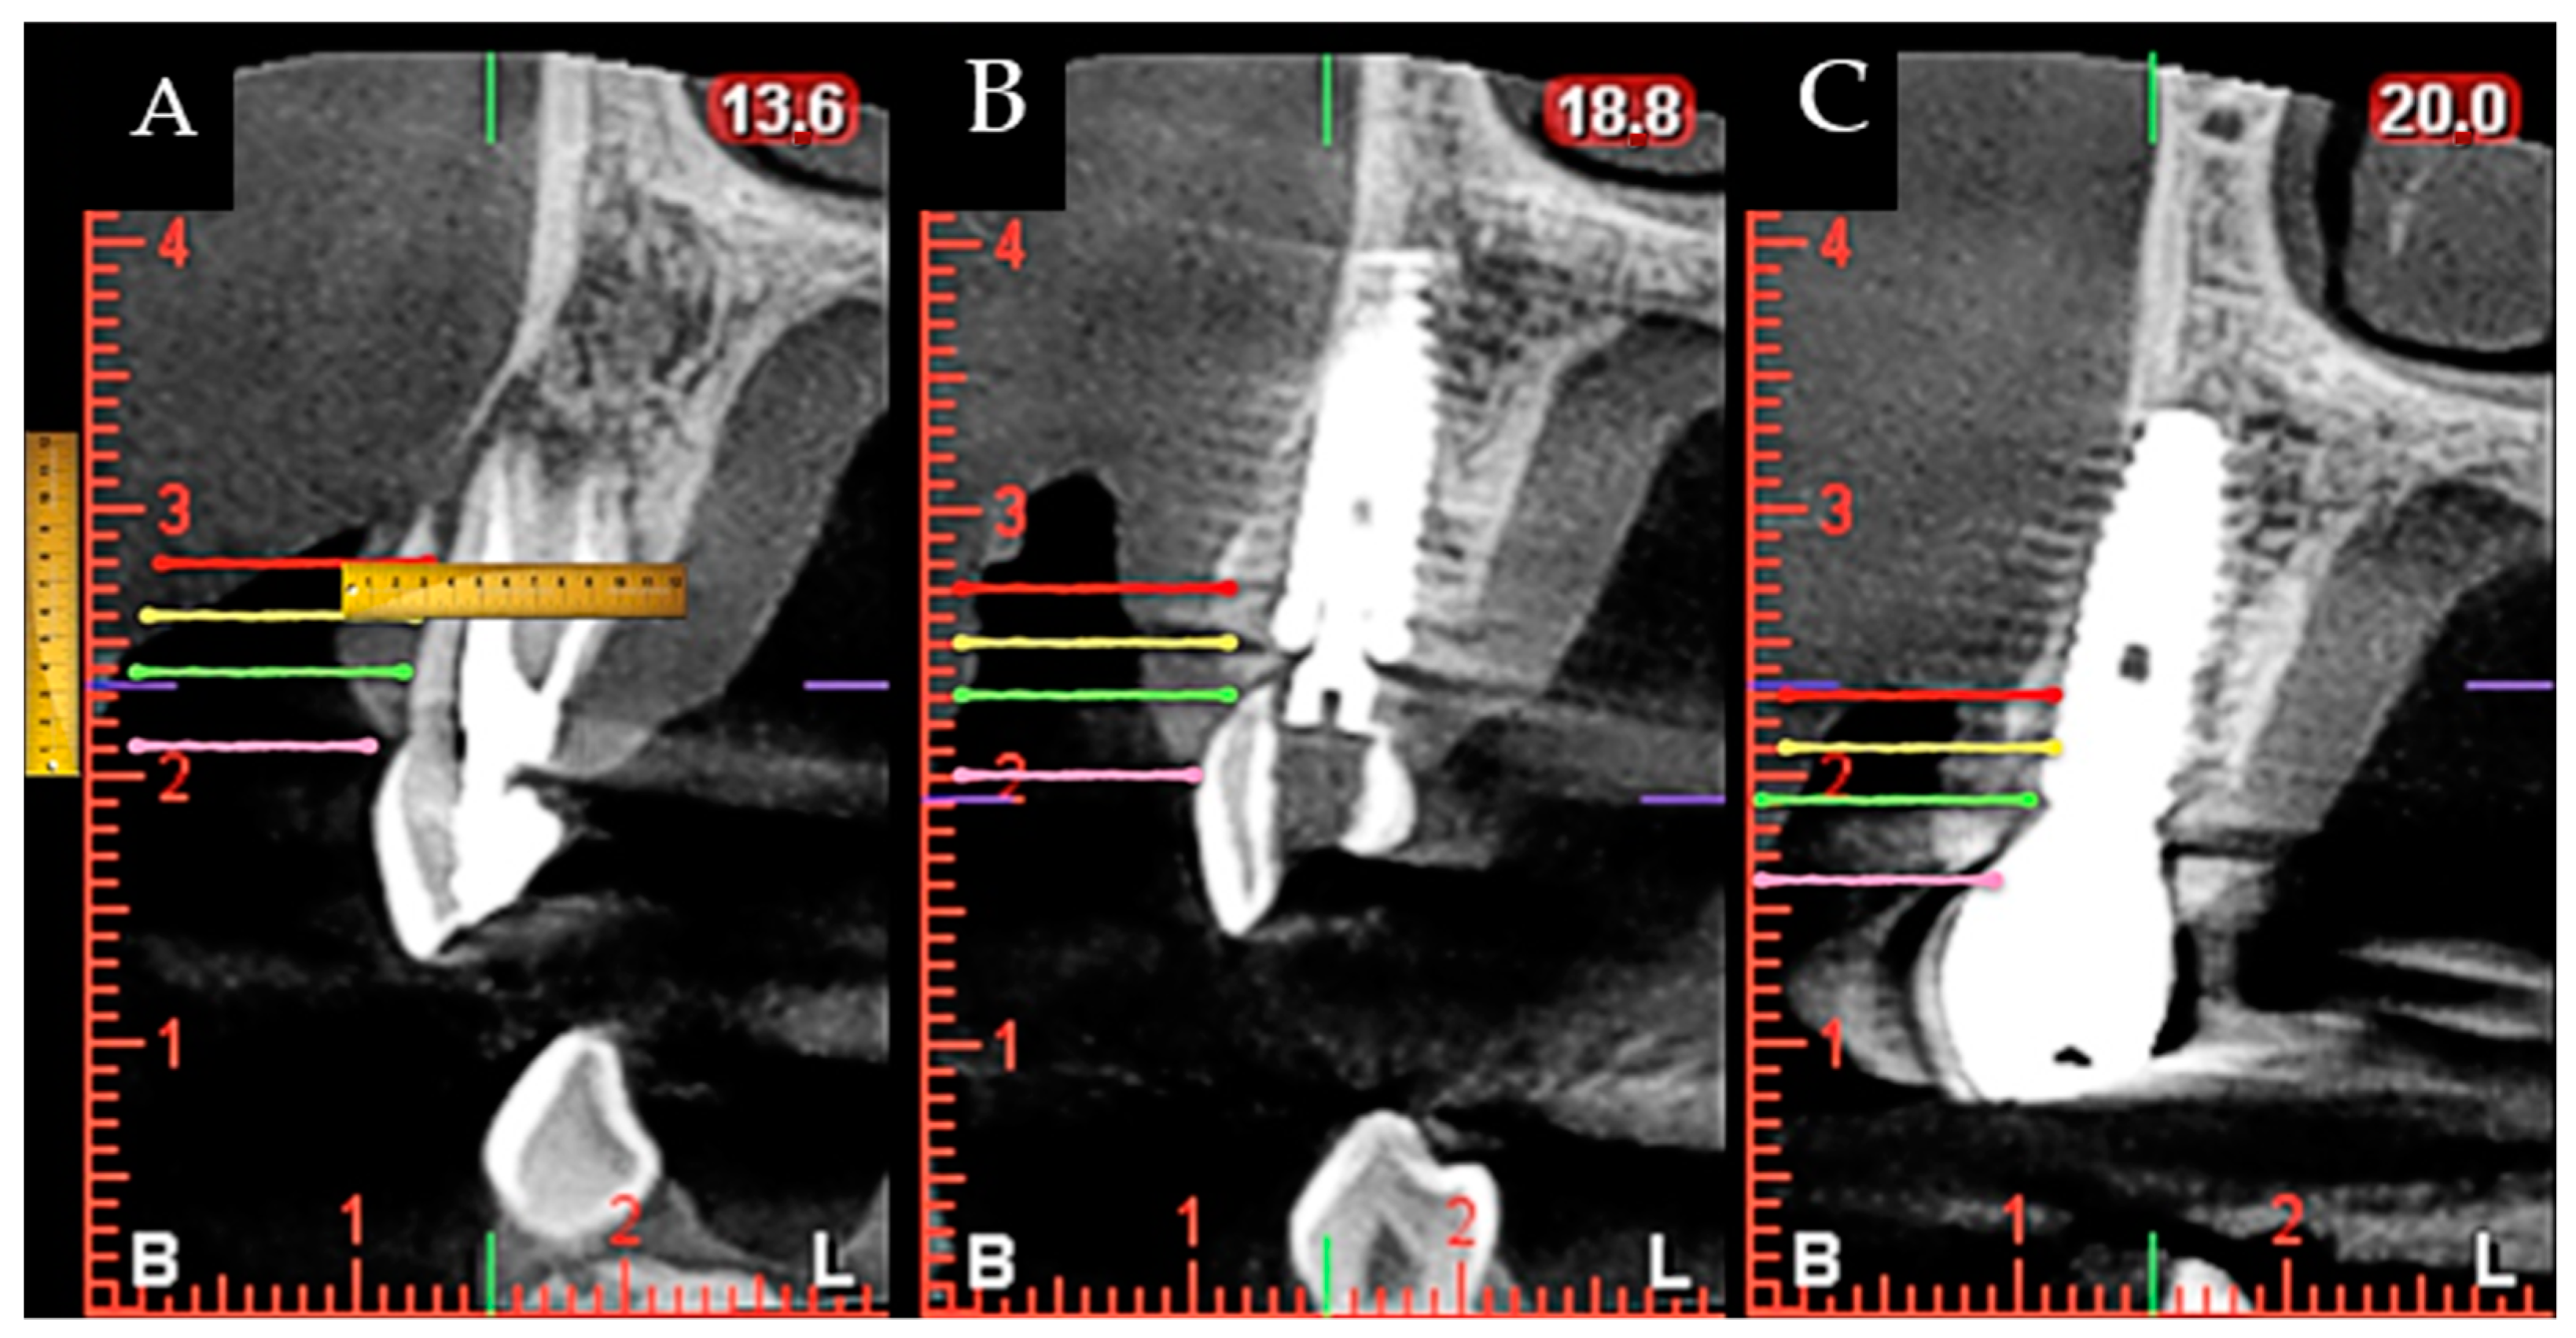

During surgery and implant placement, a connective tissue graft was harvested, and/or a socket shield technique was carried out. Both techniques are described below. The bone crest dimensions were analyzed with a periodontal probe during surgery. Based on previous publications, the changes in peri-implant tissues volume were measured using a CBCT radiological study (Planmeca Promax 3D, Helsinki, Finland) immediately after implant placement and at check-ups by a single well-trained examiner (R Gómez-Meda) to ensure measurement consistency [21]. CBCT images were undertaken based on the radiological images of the Planmeca viewer software (Planmeca Romexis v. 3.8.3.R, Helsinki, Finland) (Figure 1 and Figure 2). The study was undertaken in Meda Dental Clinic (Ponferrada, Leon, Spain).

Figure 2. Image that identifies the locations of the measurements made in the CBCT during the study. CBCT measurement of the gingival margin (pink line), and marks at 3, 5, and 7 mm (green, yellow and red lines, respectively); crestal height location; distance from the bone crest to the implant platform; tunneling of a connective tissue graft; suture; one-year postoperative. (A) Preoperative situation; (B) Immediate postoperative situation; (C) One year follow-up.